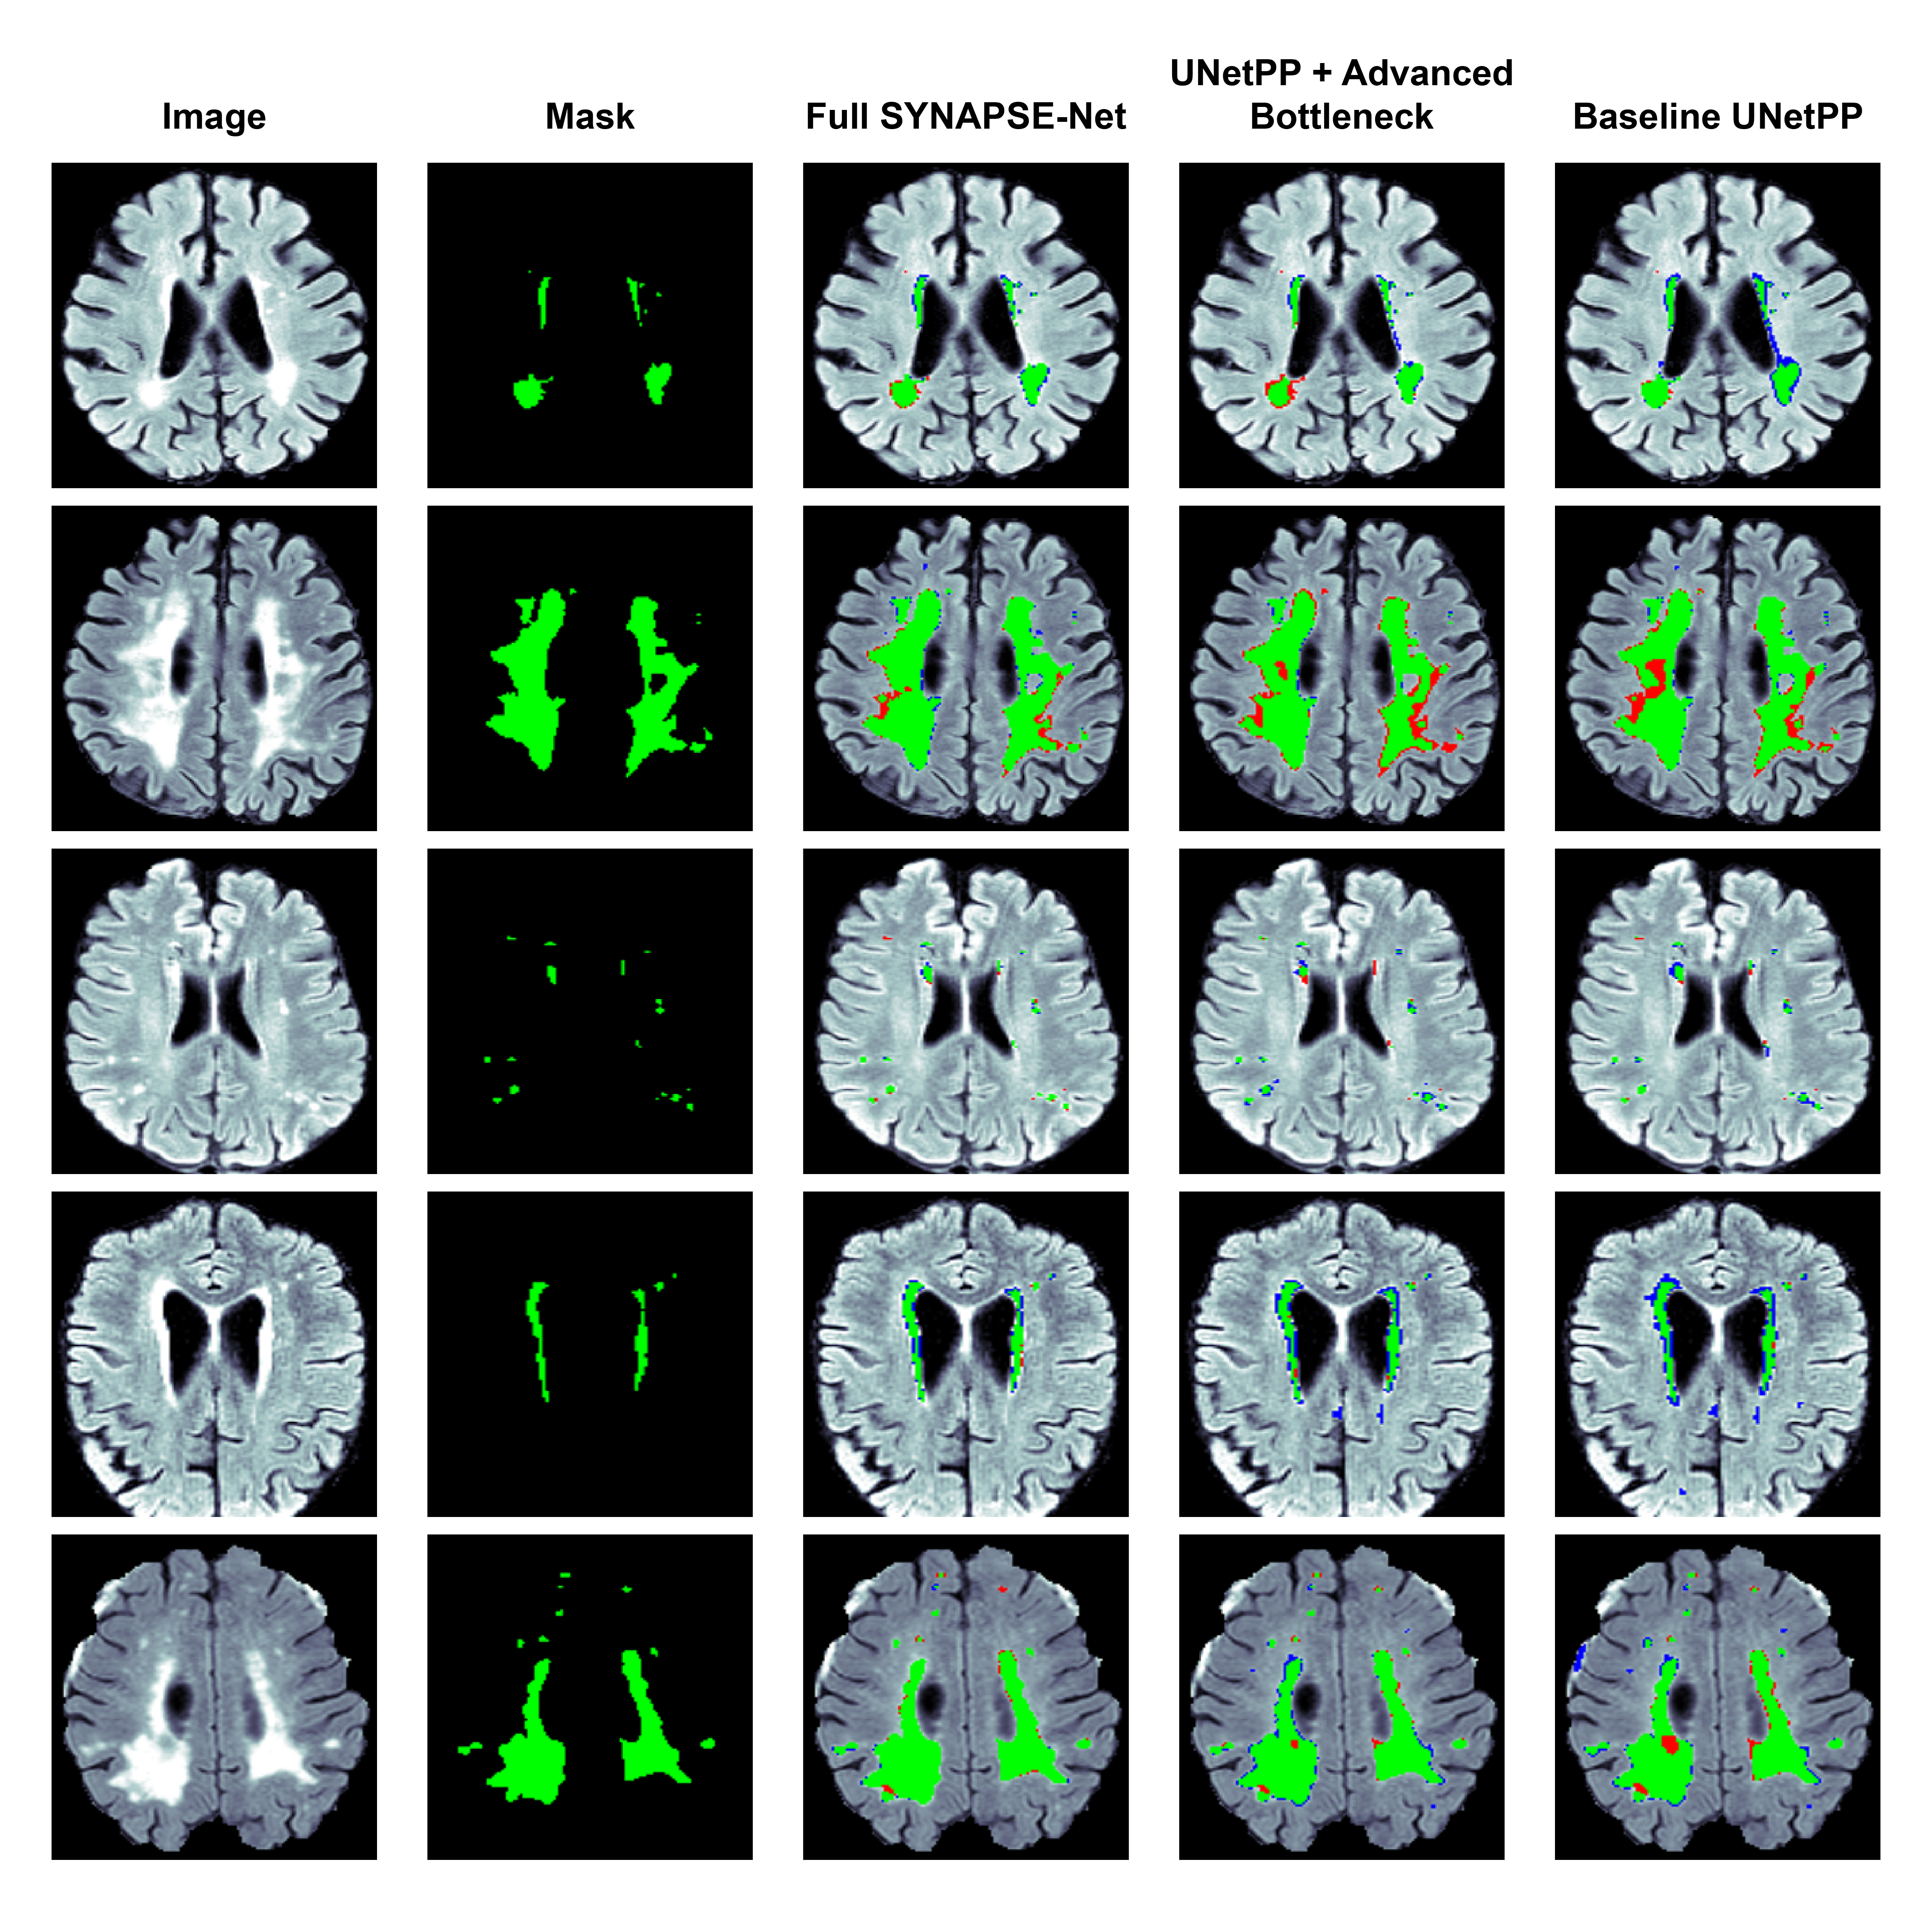

3.5.2 Ablation Study of Architectural Components

The next study evaluated the effects of our novel architectural components, using the complete training pipeline on each model. The quantitative findings are shown in Table 4 and qualitative examples provided in Fig. 5.

Refer to caption

Figure 5: Qualitative results of the architectural ablation study on the WMH dataset. Segmentation overlays show true positives (green), false negatives (red), and false positives (blue).

Our baseline (1), a standard UNet++, had a satisfactory DSC, but its large HD95 value and its instability clearly reflect its weaknesses in precision. The qualitative results in Fig. 5 are typical where the baseline model detects larger lesions but has noisy poorly defined borders and severe under-segmentation, especially for small lesions. Next, we evaluated the influence of our (2) advanced bottleneck that incorporates the multi-stream encoders, Swin Transformers, and the CMAF module. This addition resulted in a substantial boost in performance in a way that the mean DSC and the HD95 improved significantly. The reason for this improvement lies in the ability of the Swin Transformer in characteristic modeling of long-range spatial context as well as the intelligent multi-modal fusion capability of the CMAF module. Finally, the (3) full SYNAPSE-Net was assessed, which integrated our novel hierarchical gated decoder. The highest improvement was again noted in the HD95 measure, reducing by around 40%. This provides conclusive proof that hierarchical gating mechanism plays a significant role in achieving excellent geometric fidelity. By implementing high-level semantic features as a means of modulating the passage of low-level spatial information, the decoder defines intricate lesion borders more accurately. This finding is evident visually in Fig. 5, where the full model produces the finest boundaries with an ability to detect small subtle lesions missed by preceding frameworks. Additionally, as evident from the boxplots in Fig. 6, the standard deviation of all metrics reached their lowest points, demonstrating that the complete architecture is the most robust and reliable.